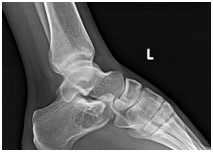

Twenty four year old male presented to us with left heel pain for nine weeks of duration. The onset of the pain was insidious and aggravated by weight bearing and prolonged standing. It was relieved with the use of analgesics and limb rest. There was no history of preceding trauma or rest pain. On examination there was no local swelling and skin changes. Deep tenderness was present over anteromedial aspect of calcaneum. Plain radiographs of the heel revealed well defined, lytic lesion in the calcaneum. Computed Tomographic scan of the same showed lytic lesion in the in the body of calcaneum just below the posterior facet. Provisional diagnosis of benign bone tumor was made and patient was planned for curettage and bone grafting.

Intraosseous lipomas are diagnosed with plain radiography and CT scan (Figure 1) (Figure 2A) (Figure 2B). Mainstay of treatment is conservative; however surgery is indicated in severe pain not responding to conservative treatment, impending pathological fracture and malignant transformation (Figure 3). Treatment for these tumors is curettage and bone grafting (Figure 4) with good prognosis.8–10

Figure 2 CT Scan of ankle showing lytic lesion in calcaneus.